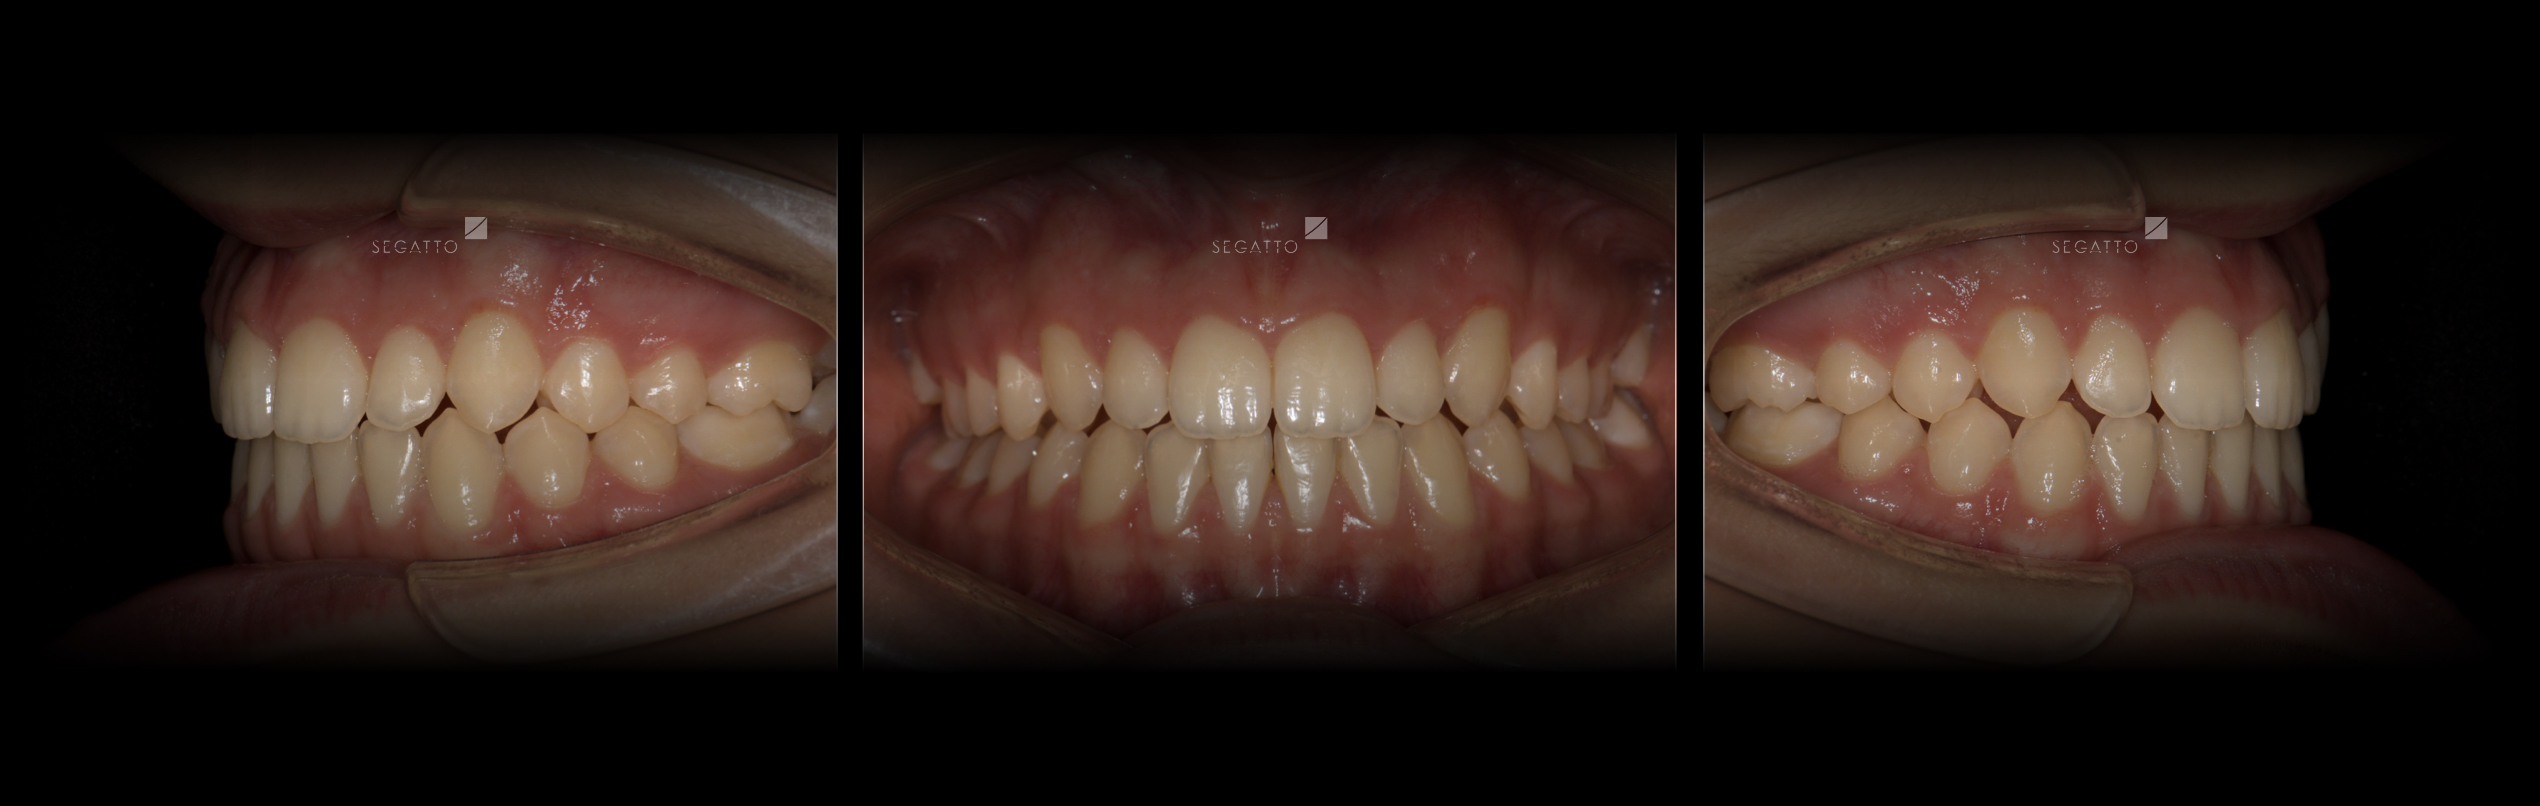

Orthodontics

Cases